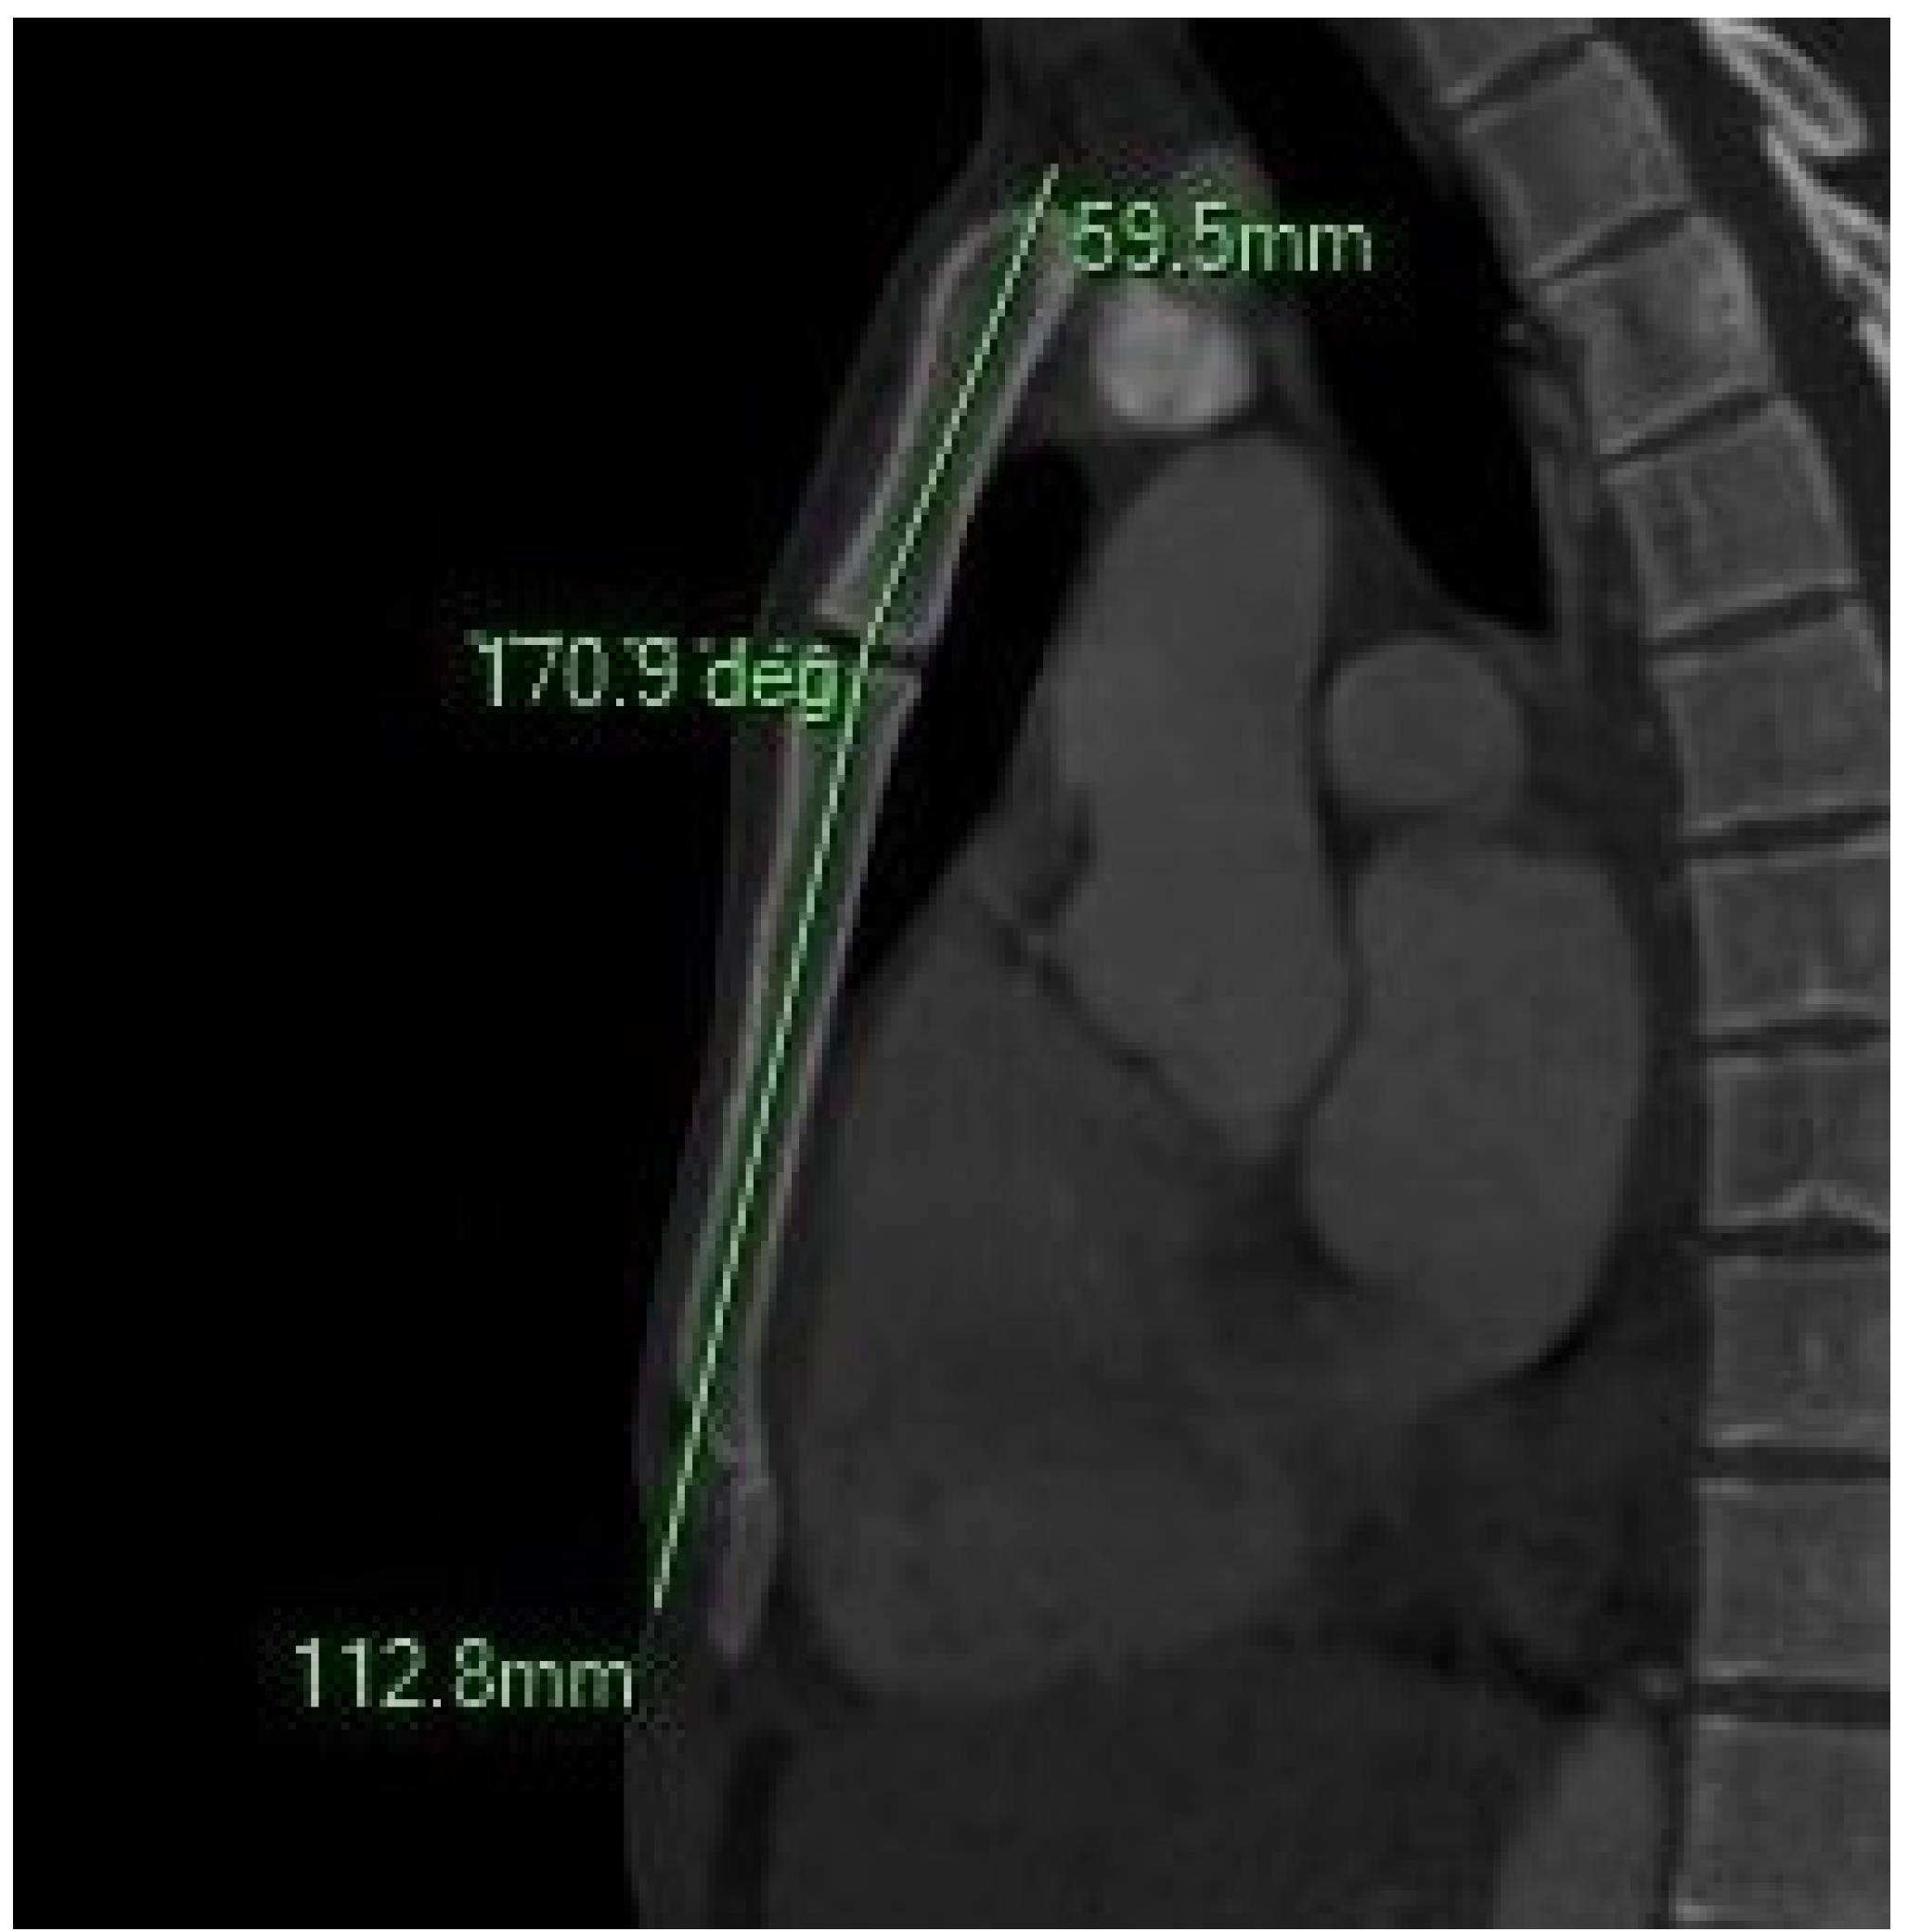

Figure 3.

The sagittal MIP MPR image illustrates the sternal angle.

- Sternal Angle (SA): Formed between the following:

- A line parallel to the body and intersecting the midpoint of the JN.

- A second line parallel to the body and intersecting its midpoint.